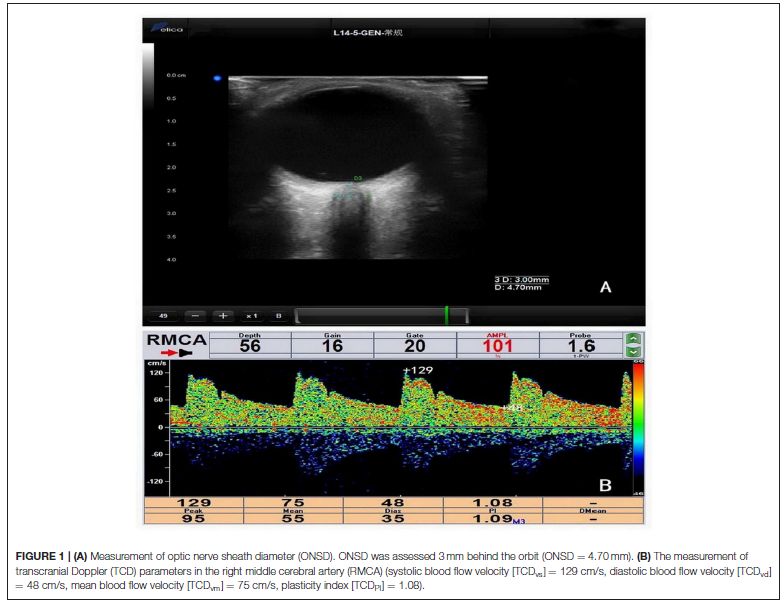

方法:研究對象為2015年8月1日到2015年10月31日在我院神經(jīng)內(nèi)科就診,可疑高ICP需進(jìn)行腰椎穿刺的患者,在腰椎穿刺之前由2名經(jīng)驗(yàn)豐富的超聲醫(yī)生進(jìn)行ONSD檢測,運(yùn)用Philips超聲系統(tǒng)9-3MHz線陣探頭輕柔地置于患者閉合的眼瞼上,進(jìn)行橫斷面及矢狀面掃查,保存雙側(cè)視神經(jīng)鞘清晰的圖像。于球后3mm處測量ONSD,每個(gè)掃查方向測量兩次。根據(jù)ICP結(jié)果患者被隨機(jī)分為2組:第1組(200<ICP≤300mmH2O),第2組(ICP> 300 mmH2O)。高ICP的患者進(jìn)行常規(guī)治療,我們在1個(gè)月內(nèi)復(fù)查患者的ONSD和ICP,分析入院時(shí)ONSD和ICP之間的相關(guān)性,比較治療前后ONSD以及ICP的變化情況,分析△ONSD和△ICP之間的相關(guān)性,(△ONSD和△ICP是治療前后ONSD和ICP的變化值)。

結(jié)果:我們共收集了60例患者(37例高ICP患者),入院時(shí)ICP與ONSD密切相關(guān)(r= 0.798,P<0.001)。其中25例高ICP患者(平均年齡35.16±12.4歲;男性13例)完成了隨訪。治療前后ONSD存在顯著性差異(P<0.001)。△ICP和△ONSD的均值分別為126.64±52.51mmH2O(范圍:20~210mmH2O)和1.0±0.512mm(范圍:0.418~ 2.37 mm)。△ONSD與△ICP呈正相關(guān)(r=0.702,P<0.001)。兩組患者治療后ICP及ONSD均恢復(fù)至正常范圍,且兩組患者ONSD的均值無顯著性差異。

Background/Aims: Non-invasive measurement of intracranial pressure (ICP) usingultrasound has garnered increasing attention. This study aimed to compare the reliability of ultrasonographic measurement of optic nerve sheath diameter (ONSD) and transcranial Doppler (TCD) in detecting potential ICP elevations.

Methods: Patients who needed lumbar puncture (LP) in the Department of Neurology were recruited from December 2016 to July 2017. The ONSD and TCD measurements were completed before LP.

Results: One hundred sixty-five participants (mean age, 41.96 ± 14.64 years; 80 men; 29 patients with elevated ICP) were included in this study. The mean ICP was 170 ± 52 mmH2O (range, 75–400 mmH2O). Univariate analyses revealed that ICP was non-significantly associated with TCD parameters and significantly associated with ONSD (r = 0.60, P < 0.001). The mean ONSD of the elevated ICP group was significantly higher than that of the normal ICP group (4.53 ± 0.40mm vs. 3.97 ± 0.23mm; P < 0.001). Multivariate linear regression determined that the difference between ICP and ONSD is significant.

Conclusions: In the early stage of intracranial hypertension, ONSD is more reliable for evaluating ICP than TCD.